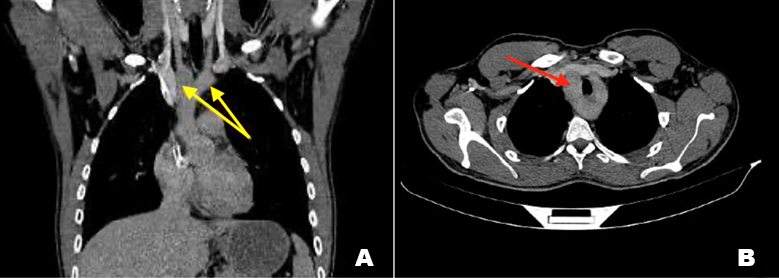

We report a case of a 27-year-old male patient, chronic smoker, presenting to our department for difficulties in swallowing evolving for several years never explored. Upper gastrointestinal (GI) endoscopy was normal. Contrast enhanced thoracic CT scan was realized showing a double aortic arch (DAA) with the ascending aorta seen splitting into the right arch and the left arch (Figure 1A). The double arch forms a vascular ring with compression of the proximal esophagus posteriorly as well as abutment and slight compression of the trachea (Figure 1B). The right and left arch have the same diameter, and each one gives rise to the ipsilateral subclavian and common carotid arteries (Figure 2). Then both arches unite posteriorly and form the descending aorta. Our scan showed no other cardiac anomaly.

Figure 1: CT C+ portal phase coronal reconstruction showing the ascending aorta splitting into a right arch and a left arch (yellow arrows). (B) CT C+ portal phase axial plane showing both aortic arches forming a vascular ring with compression of the trachea.